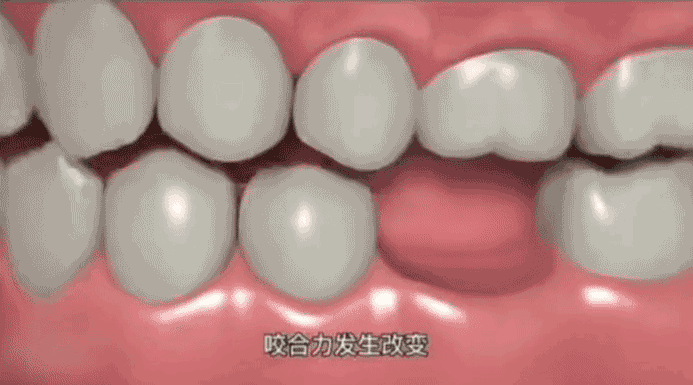

牙齿缺失后不及时修复,不仅直接影响咀嚼、发音的功能,伴随而来的还有其他牙齿的变化,导致出现对𬌗牙伸长、邻牙移位、咬合紊乱、关节紊乱等一系列问题,甚至引发一些意想不到的全身性问题。

牙槽骨萎缩,邻牙移位,导致咬合紊乱